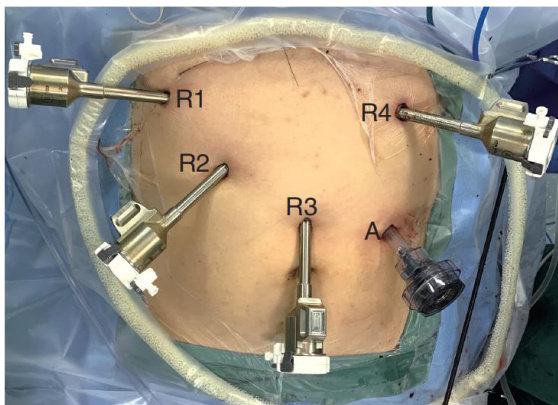

摘要目的:探讨人工智能(AI)辅助下多模态超声联合促甲状腺激素受体抗体(TRAb)、血管内皮生长因子(VEGF)检测对甲状腺结节的精准诊断及其临床价值评估。方法:选取2023年1月—2024年9月于唐山市人民医院就诊的129例甲状腺结节性疾病患者为研究对象,采用AI辅助下多模态超声检查【AI常规超声 + 彩色多普勒血流成像(CDFI) + 实时剪切波弹性成像(SWE) + 超声造影(CEUS)】,以术后病理结果为金标准,将研究对象分为良性组( n=82 )与恶性组( n=47 )。检测血清TRAb、VEGF水平,并比较两组各项超声指标及血清指标水平,分析AI辅助下多模态超声检查与血清指标及联合预测对甲状腺结节的诊断价值。结果:AI辅助下多模态超声联合TRAb、VEGF检测与病理结果完全符合率为 98.45%( 127/129 ),其检测甲状腺结节的灵敏度、特异度、阳性预测值及阴性预测值均显著高于TRAb、VEGF单一检测( P<0.05 )。以临床病理结果为金标准,TRAb、VEGF、AI辅助下多模态超声及联合预测对甲状腺结节的诊断效能分析(AUC, 95%CI )依次为(0.849,0.773\~0.926),(0.883,0.814\~0.952),(0.927,0.872\~0.982)和(0.983,0.956\~1.000),与 AZ=0.5 相比,均有显著差异( P<0.05 )。结论:在甲状腺结节良恶性诊断中,借助AI技术整合多模态超声特征与血清TRAb、VEGF指标,可显著提升诊断准确性,具备重要临床应用价值。